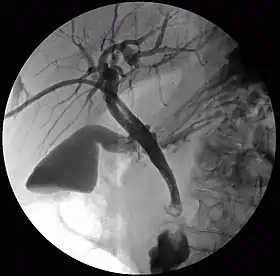

![]() تصوير الأقنية الصفراوية عبر الكبد عن طريق الجلد | |

- تصوير الأقنية الصفراوية عبر الكبد عن طريق الجلد (PTC): فحص الكبد والأقنية الصفراوية بالأشعة السينية، ويُجرى ذلك عبر إدخال إبرةٍ رفيعةٍ في الكبد وحقن مادة تباينٍ فيها للمساعدة على مشاهدة الانسداد الحاصل في الكبد والأقنية الصفراوية.